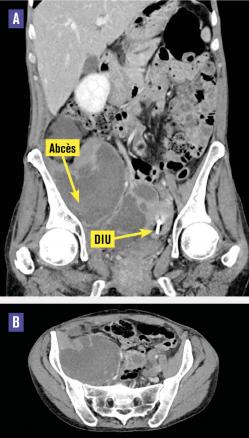

Cette femme de 48 ans était hospitalisée pour une fièvre associée à une douleur abdominale depuis plusieurs jours. L’examen clinique montrait une défense du flanc droit. Le toucher pelvien était normal chez cette patiente ayant un dispositif intra-utérin (DIU) au cuivre, posé il y a 5 ans. Il existait un syndrome inflammatoire biologique avec une CRP à 408 mg/L et une hyperleucocytose à 21 G/L. La tomodensitométrie (TDM) abdomino-pelvienne montrait une collection pelvienne multiloculée mesurant 30 × 37 mm communicant avec une seconde collection lobulée au sein du muscle ilio-psoas droit de 15 × 10 × 8 cm (fig. 1A et B ). Le drainage effectué sous contrôle radiologique permettait l’évacuation de 700 mL d’un liquide purulent. L’examen direct du DIU trouvait des bacilles à Gram positif branchés et la culture notait une flore vaginale avec des germes anaérobies, de nombreuses colonies d’Actinomyces turicensis (fig. 2 ) et de Streptococcus constellatus, présents également sur deux hémocultures. L’évolution était favorable sous amoxicilline (6 semaines).